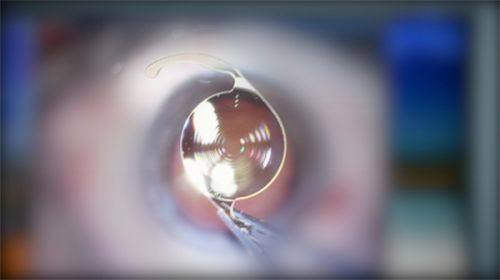

(一)德国蔡司全飞秒微创切口小

1. 医院引进了德国蔡司 VisuMax 全飞秒激光系统,这是目前海内外公认的近视矫正“金标准”设备。

2. 手术过程无需制作角膜瓣,仅通过 2-4 毫米的微小切口即可完成,极大降低了术后干眼和角膜移位的风险。